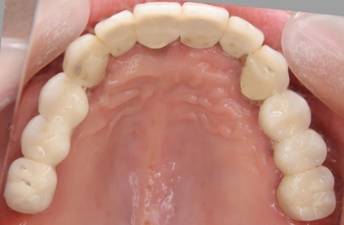

術後。上部構造はハイブリッドレジンです。しっかり嚙めるようになり喜んでいただきました。

上顎

下顎

上部構造装着後6年。ハイブリッドレジンを使用したため、少し艶がなくなってきました。上部構造の材料には金属、ハイブリッドレジン、セラミックなどがあります。セラミックはきれいですが欠けやすいため、最近はフルジルコニアを使っています。

上顎 少しすり減ってきました。

下顎。12か月に一度メインテナンスをしています。